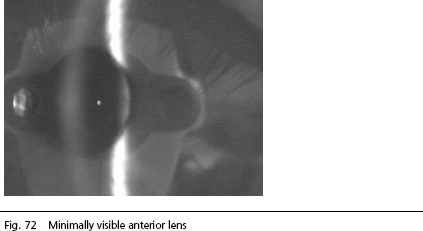

IOLMaster Arizona Note: It will suffice if a relatively small section of the lens is visible. The picture below shows an alignment that permits accurate measurement.

Phakic Eye

The image is sufficient for the calculation of the anterior chamber depth. (In the photo above, the front side of the IOL Master is visible as a non-disturbing artifact).